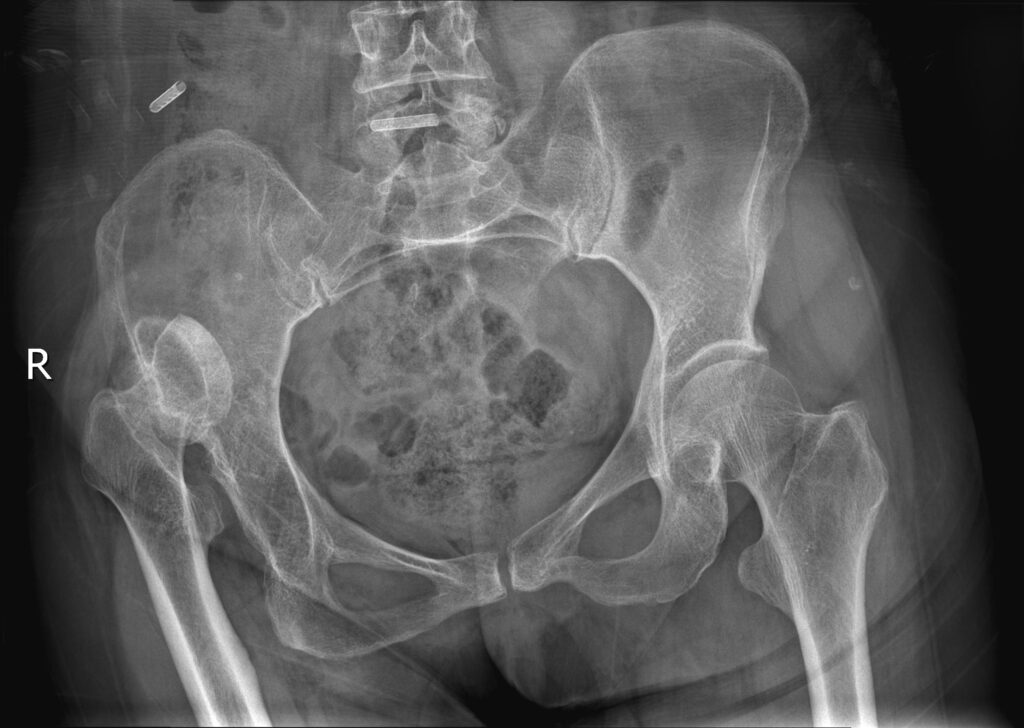

先天性髋关节脱位股骨头在假臼中再脱位(Congenital dislocation of the hip joint leads to re-dislocation of the femoral head in the false socket)